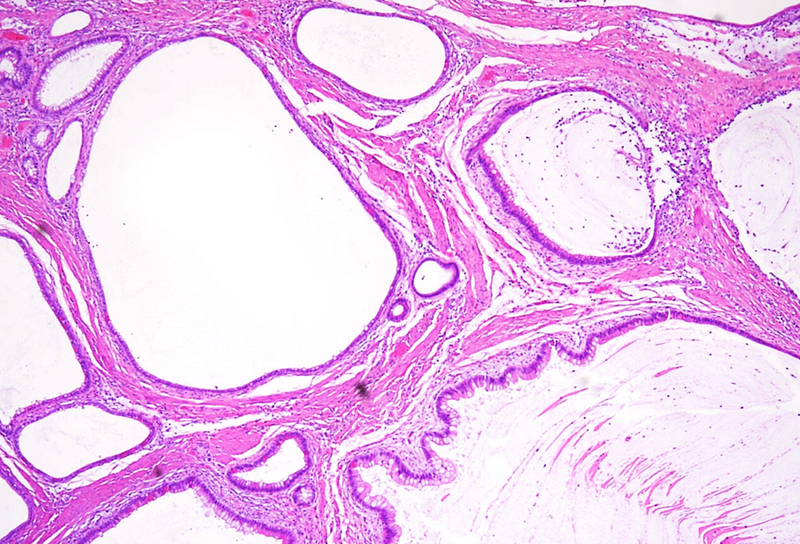

Polypoid lesion at the anorectal junction in a 47 year-old male.

Proctitis cystica profunda.

Microscopically, one specimen disclosed cystically dilated structures of variable size underneath regular colonic  / anal mucosa (Panels A-B). The cysts are filled with mucin, and the epithelial lining is of intestinal type, showing reactive changes, yet no dysplasia in the presence of mixed unspecific inflammation (Panels C-D).

Histologically, it is characterized by the presence of either localised, segmental, or diffuse mucus-filled cysts of the deep submucosa and even muscularis propria. Size of the cysts may differ, depending on localisation and diffuse morphology, lesions can measure up to even 2 cm. The lining epithelium lacks atypia, with only minor nuclear irregularities in case of secondary inflammatory changes. The overlying mucosa is intact. Surrounding areas may contain fibrosis and hemosiderin laden macrophages. The cysts may rupture causing mucin dissemination into the surrounding tissue, potentially followed by degenerative calcification. Differential diagnosis mainly includes mucinous adenocarcinoma, which may be identified by nuclear dysplasia and/or desmoplastic response.